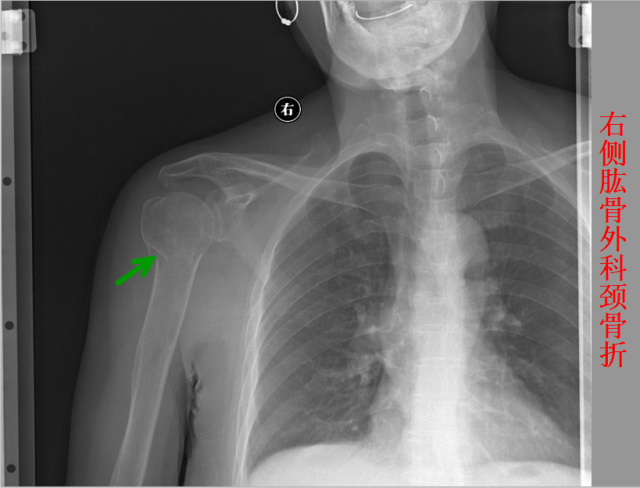

骨折篇

定义:骨折{Fracture}是指骨的完整性和连续性的折裂或粉碎。包括创伤性骨折、疲劳性骨折和病例理性骨折。 临床上以创伤性骨折*常见。